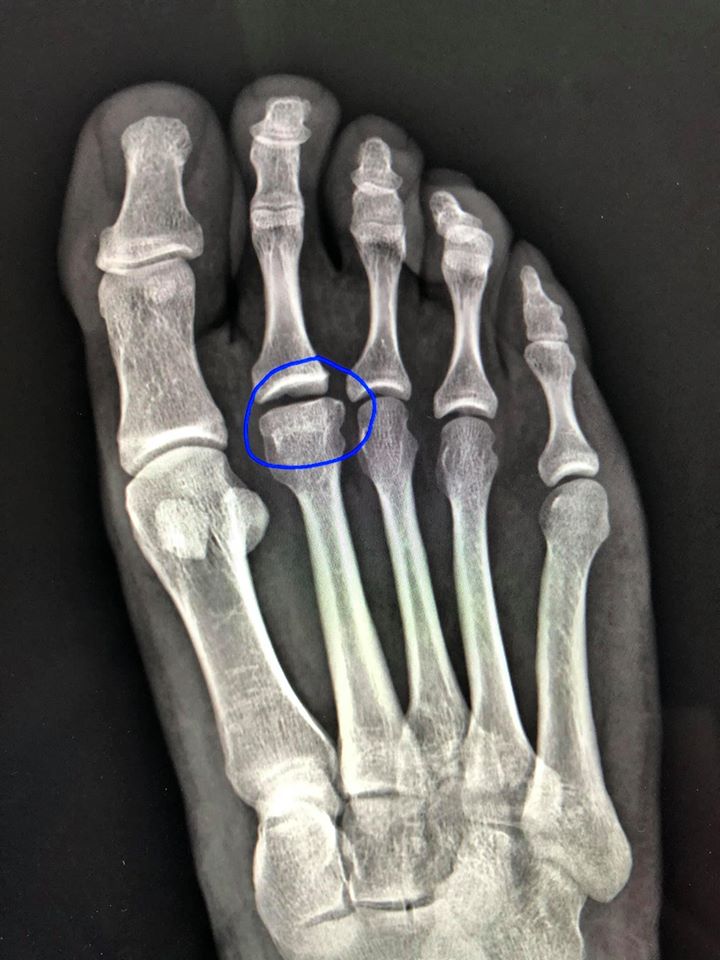

X-rays and MRI scans can help to identify this condition. Upon diagnosis, podiatrists can offer non-operative treatment to decrease the symptoms and delay progression of the disease. This includes padded inserts and custom shoes that take pressure off of the affected area when walking. Corticosteroid injections may be used to reduce inflammation and pain during flare-ups. Surgical intervention may be needed for patients with advanced Freiberg’s disease if conservative treatments are ineffective.

Symptoms of Freiberg infraction include pain that occurs with weight bearing activity, swelling in the forefoot, and stiffness or reduced range of motion in the forefoot. Diagnosis includes physical examination and x-rays of the foot. MRI or CT scans may also be useful in evaluating soft tissue and bone changes. Nonoperative treatment involves reducing foot pressure and unloading the metatarsal head with the use of orthotics, rest, crutches and activity modification. Surgical options include dorsal closing wedge osteotomies, osteochondral transplantation and resection arthroplasty.

Symptoms begin gradually and include pain under the ball of the foot, usually on one side and worse with activities that bend the toe. X-rays and other diagnostic tests can help your doctor determine if Freiberg infraction is present.